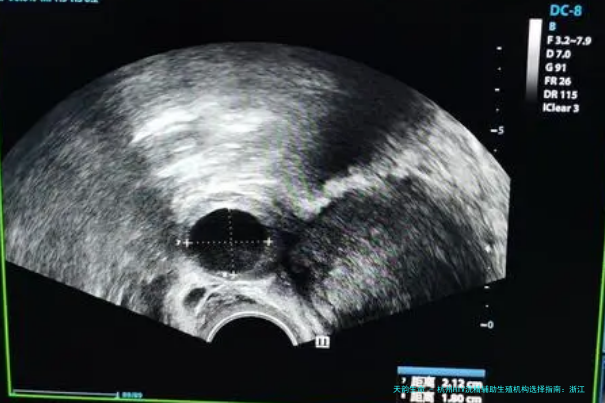

HIV洗精,是一种精子处理技术。它通过特殊的离心和洗涤过程,将精子与可能包含病毒的精浆分离,进而取得到不含HIV病毒的健康精子。这些精子随后用于试管受孕(试管婴儿)或卵胞浆内单精子注射(显微受精技术),以确保胚胎不受病毒感染。这项技术为HIV阳性男性提供了生育健康后代的可能性。